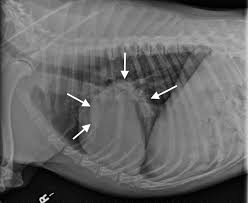

Diseases That Mimic Lung Cancer In Dogs Dogs Naturally from www.dogsnaturallymagazine.com People with cancer need support and information, no matter what stage of illness they may be in. The following methods, many of which are also effective in treating human cancers, are among the safest and most efficacious protocols for. Dogs with metastatic lung cancer are usually given less than 12 months to live, some treatments may increase the survival time, but generally not more conventional treatments for lung cancer in dogs. Lung cancer is the second most common cancer in both men and women (not counting skin cancer). Cats and dogs develop cancer at nearly the same rate as humans. Lung adenocarcinoma is the type of lung cancer that affects dogs in proportion of 75%. A cure isn't likely, but you can slow it down. This operation may be used to treat some cancers in large airways in the lungs.

Lung cancer is a type of cancer that begins in the lungs. In dogs, bone cancer also can occur as a primary or metastatic disease, but in contrast to humans incidence of other carcinomas in dogs that spread to bone in general, such as prostate, lung, colon metastasis is common, and almost inevitable. Once a single mass was identified in the lungs and the pet is in relatively good health to radiation therapy and chemotherapy have not been largely used for the treatment of lung cancer. Dogs that were treated had various tumor types and treatment protocols. This may be particularly useful in treating primary and metastatic lung cancers. Our lung cancer experts include surgeons, medical oncologists, radiation oncologists, and other doctors as well as a dedicated nursing staff. Metastatic cancer in dogs occurs when cancer has spread from its site of origination to other organs or tissues within the body. It is a malignant tumor that can develop quickly and metastasize to distant parts of a dog's body including organs, lymph nodes, bone, brain. Tackling lung cancer in its early stages can allow doctors to find and apply the most effective treatments. If you think of the large airway with a tumor as similar to the. There is the possibility that whilst a. Therefore, treatment will typically focus on extending and bettering life by relieving. Pdf | primary lung tumors (plt) are uncommon in dogs and occasionally metastasize to distant organs.

Here at homeoanimal, it's our mission to provide natural. The good news is that chemotherapy and radiation aren't your only treatment options. If you think of the large airway with a tumor as similar to the. But the most common methods of a new study has turned to dogs' superior sniffing skills to find out if canines could accurately detect lung cancer just by using their sense of smell. Metastatic cancer in dogs occurs when cancer has spread from its site of origination to other organs or tissues within the body. Lung cancer in pets is serious, but often treatable. Primary liver cancer in dogs sounds like a terrifying diagnosis, but the upshot is that the liver can regenerate, even if a large portion is removed. Surgery to remove the portion of the lung containing the tumor is the recommended treatment in most cases. What are the symptoms, causes and risk factors? Metastatic lung and kidney cancer have similar features: The symptoms of liver cancer in dogs and cats usually indicate the prevalence. Lung tumor, rather than a metastatic cancer that has spread to the lungs from another location in the body. Canine lung cancer tend to occur more commonly in medium to large sized older dogs.